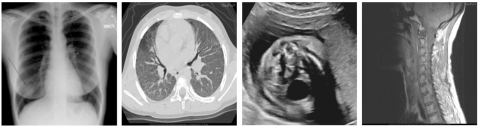

A comprehensive evaluation of the proposed watermarking scheme was carried out using the publicly accessible COVID-19 chest X-ray database [18]. While CT, MRI, and ultrasound images were obtained from MedPix [19-21]. The evaluation was performed on a Windows 10 system using MATLAB R2023b Update 3, running on an Intel Core i5-6500 CPU (3.2 GHz) with 8GB of RAM. To ensure experimental consistency and mitigate variations arising from dimensional differences, all images were standardized to 512×512 pixels. Figure 4 presents representative examples of these uniformly sized host images from different categories used in the watermarking process. A 32×32 pixel image, representing 1,024 bits of information, was employed as the watermark (Figure 5). This configuration aligns with typical data capacity requirements for securing medical imagery, as documented in the relevant literature [22].

Figure 4. Sample cover medical images